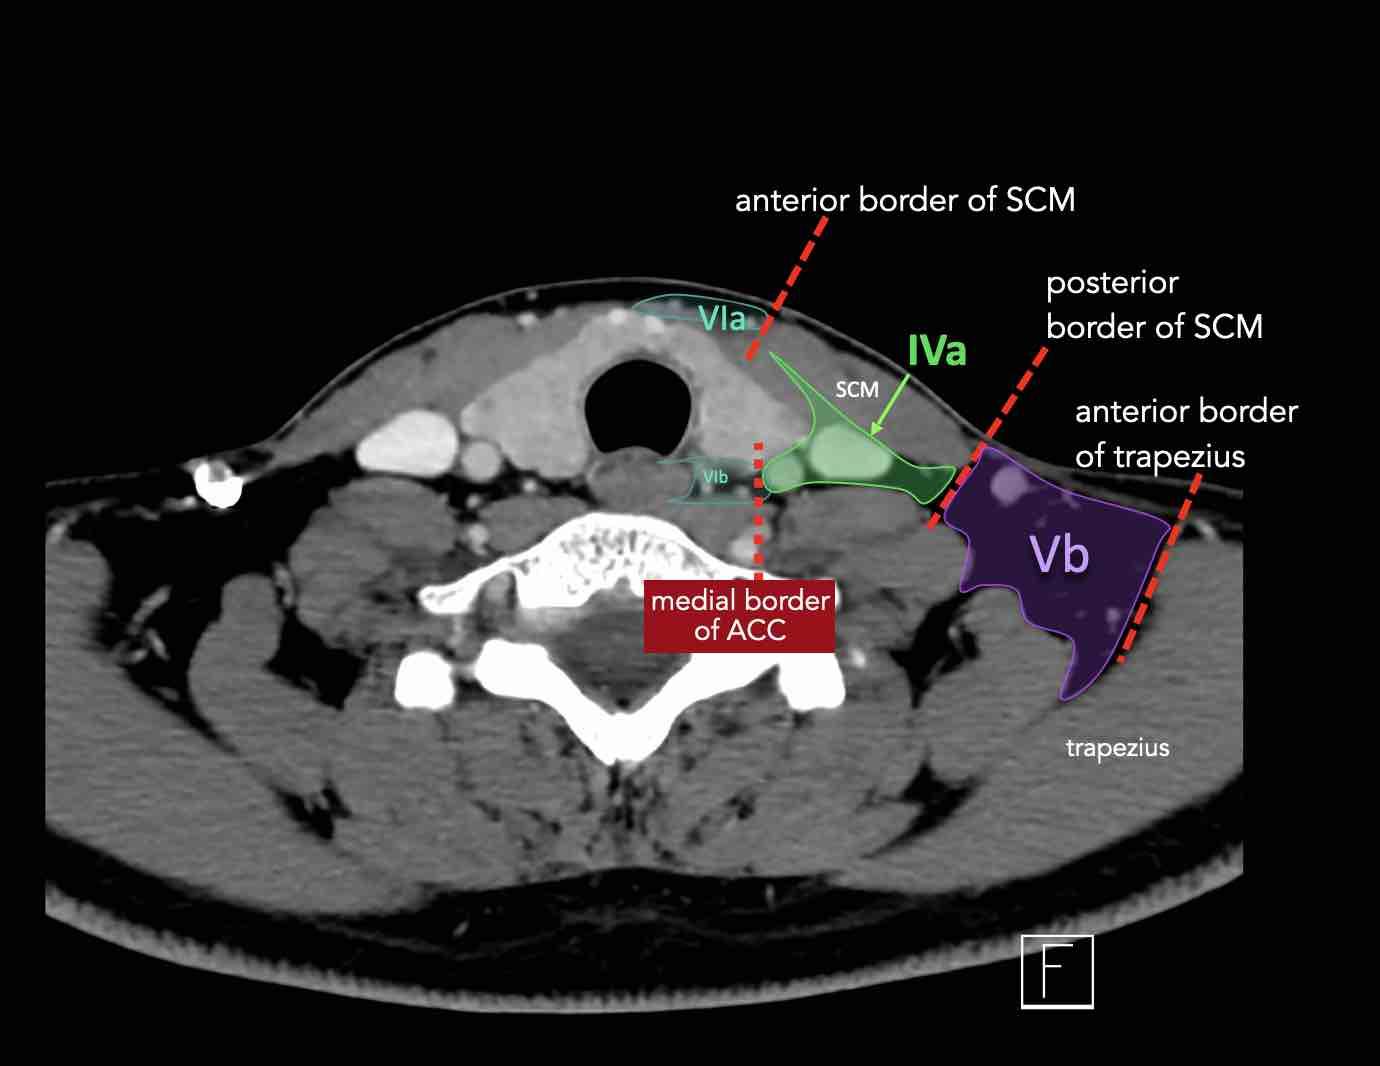

CT Scan Mặt Cắt Ngang (Axial CT)

Các lát cắt CT mặt phẳng ngang tương ứng với hình minh họa tổng quan.

Các lát cắt CT mặt phẳng ngang với hình ảnh chi tiết hơn.

Nhấp vào hình ảnh để phóng to.

IV – Tĩnh mạch cảnh dưới và hố thượng đòn trong

Ranh giới giữa tầng IVa và IVb được xác định tùy ý tại vị trí 2 cm phía trên khớp ức đòn.

Tầng IVa

Các hạch này có nguy cơ chứa di căn từ các ung thư hạ hầu, thanh quản, tuyến giáp và thực quản cổ.

Hiếm gặp hơn, di căn từ khoang miệng trước có thể biểu hiện tại vị trí này với tổn thương hạch gần tối thiểu hoặc không có.

Tầng IVb

Các hạch này có nguy cơ chứa di căn từ các ung thư hạ hầu, thanh quản dưới thanh môn, khí quản, tuyến giáp và thực quản cổ.

V – Tam giác cổ sau và hố thượng đòn

Tầng V chứa các hạch của nhóm tam giác cổ sau nằm ở phía sau cơ ức đòn chũm, xung quanh phần dưới của thần kinh phụ gai sống và các mạch máu cổ ngang.

VI – Cổ trước